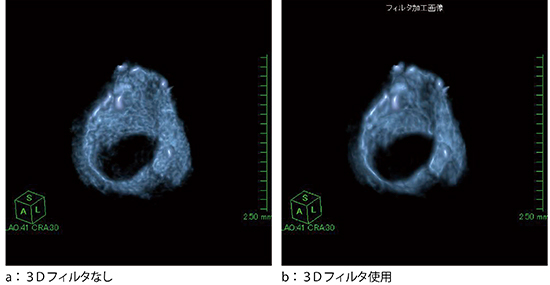

そこで,3Dフィルタを使用してオリジナル画像のノイズを低減させて,ボリュームの辺縁を滑らかに表示させる処理を行った。調整率によってフィルタのかかる割合が細かく設定でき,容易に画像確認を行うことが可能である(図5)。3Dフィルタによりノイズが低減されて辺縁が滑らかになったことで,輪状軟骨の左側壁部の骨折がより明瞭になり,内側に偏位しているのが確認できる(図6)。

図5 3Dフィルタ使用の有無による画像の比較(輪状軟骨)